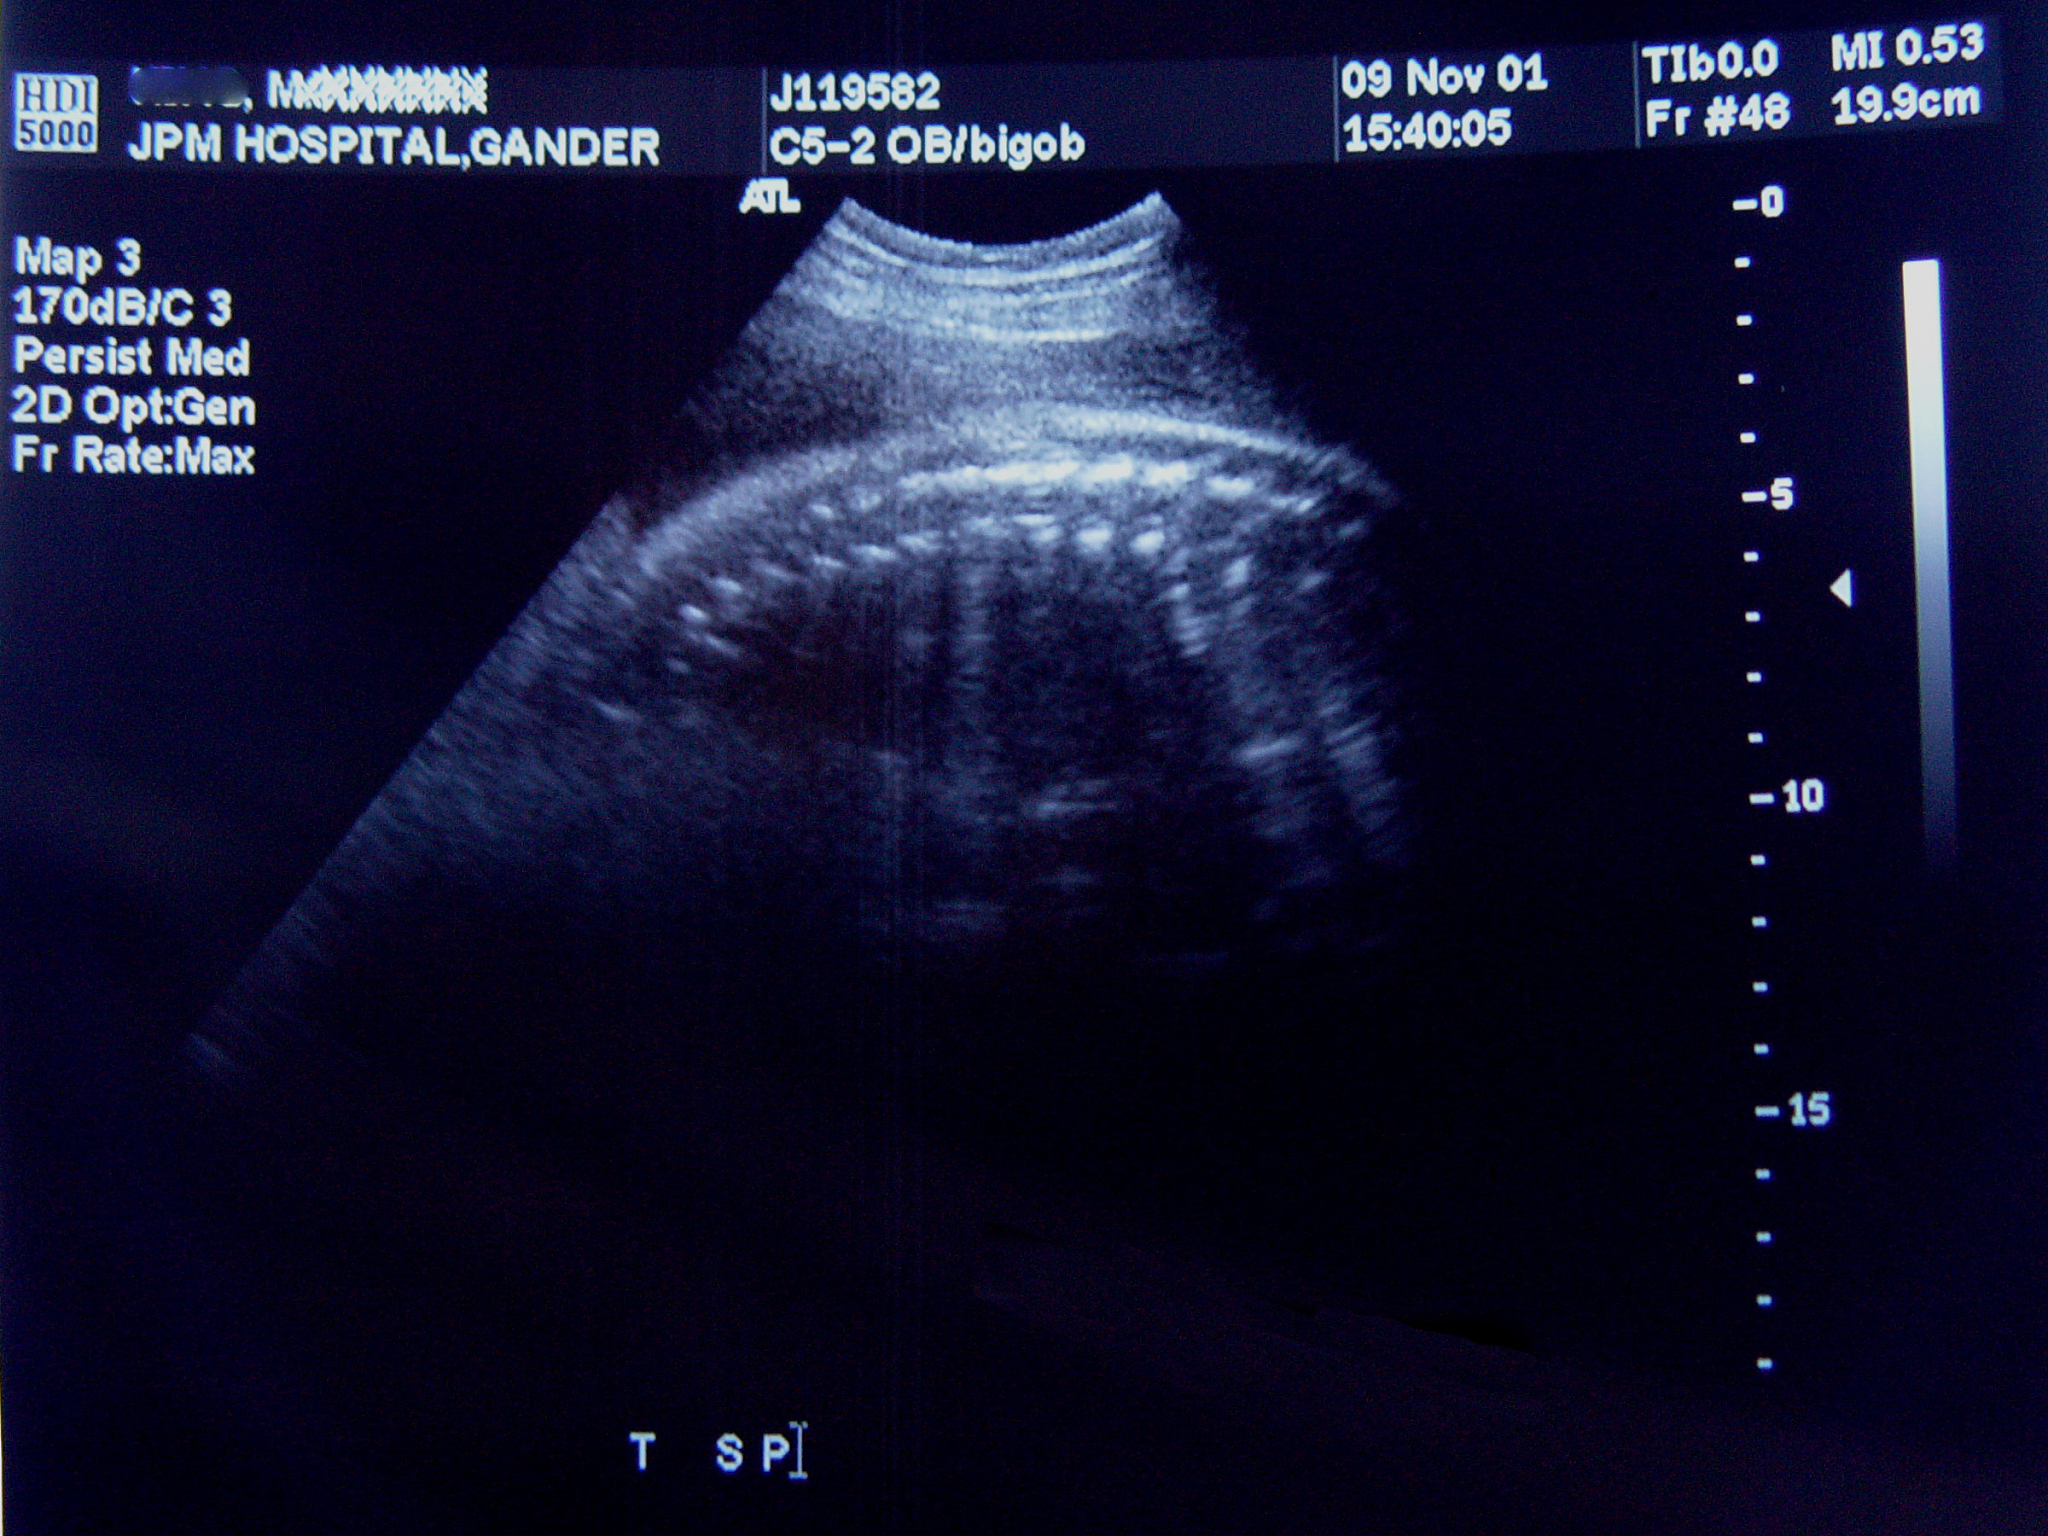

成年女性后盆腔肌性组织结构超声测量:硕士论文答辩问题

1. 为什么选择研究成年女性后盆腔肌性组织结构的超声测量\u003f 有什么实际应用价值\u003f\n\n2. 你的研究方法中使用的超声测量技术有哪些优点和局限性\u003f\n\n3. 在研究中,你是如何确保超声测量的准确性和可靠性的\u003f\n\n4. 你的研究结果是否与已有研究结果一致\u003f 如果不一致,可能的原因是什么\u003f\n\n5. 你的研究中是否考虑了样本的多样性和代表性\u003f 是否有可能存在样本偏差\u003f\n\n6. 在你的研究中,你是否考虑了其他可能影响结果的因素,如年龄、体重等\u003f\n\n7. 你的研究结果对于临床医学或其他相关领域有何启示和应用价值\u003f\n\n8. 在进行后盆腔肌性组织结构的超声测量时,你是否遇到了任何技术或方法上的困难\u003f 如果有,你是如何解决的\u003f\n\n9. 在今后的研究中,你认为还有哪些方面可以进一步改进和深入探索\u003f\n\n10. 你认为你的研究有哪些局限性\u003f 有没有可能对结果进行更全面和深入的分析或解释\u003f